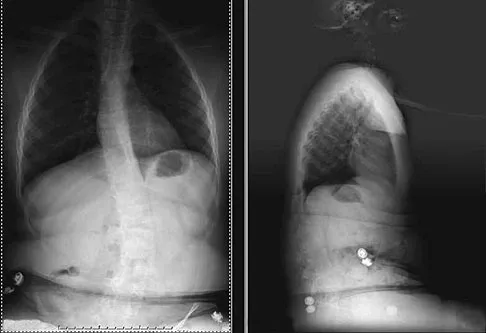

Question 41 High Yield

A 10-year-old boy with an L1 myelomeningocele has a low-grade fever and a swollen thigh that is warm to touch and erythematous. AP and lateral radiographs are shown in Figures 24a and 24b. Management should consist of

Detailed Explanation